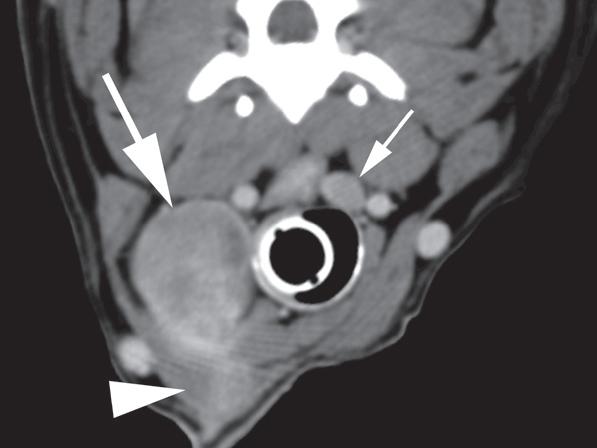

Rycina 1.11.6. Rak tarczycy i gruczolak tarczycy (pies) TK

Badanie wykonano u 12-letniej, kastrowanej samicy owczarka australijskiego z prawostronną masą w dobrzusznej części szyi. Badanie USG wykazało dużą, litą, unaczynioną masę w obrębie prawego płata tarczycy (a) oraz mniejszą, hipoechogeniczną masę w obrębie lewego płata (b). Obrazy TK przed i po podaniu środka kontrastowego (c–f) ułożone od doczaszkowych do doogonowych ukazują dużą, prawostronną, jednorodnie wzmacniającą się masę (c–f – duża strzałka) z niewyraźną granicą dobrzuszną oraz pozatorebkowym szerzeniem się i rozlanym wzmocnieniem pokontrastowym przyległych tkanek (e, f – grot strzałki). W obrazie bardziej doczaszkowym widoczny jest prawidłowy lewy płat (c, e – mała strzałka), natomiast w obrazie bardziej doogonowym jest on powiększony i ma niższą gęstość, niż można by oczekiwać, co sugeruje obecność drugiej, mniejszej masy (d, f – mała strzałka). W obrazach reformowanych wzdłuż osi długiej widać dwa małe guzki w lewym płacie (h – małe strzałki). Wyniki obrazowe potwierdzono podczas zabiegu (i, j – strzałki). Biopsja wycinkowa wykazała prawostronnego raka tarczycy z naciekaniem pozatorebkowym oraz lewostronnego gruczolaka tarczycy